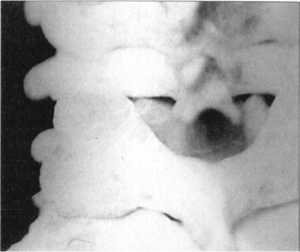

Способ Рише-Гютера - вытяжение шейного отдела позвоночника при сцепившемся

вывихе приводит к уменьшению сцепления между суставными отростками (рис. 2.12.5-2.12.8

и рис. 2.11, графа "вытяжение" - вид сзади, сбоку). При этом вертикальный

размер поврежденного сегмента увеличивается на 6,3±1,0 мм от исходного, а давление

возрастает на 300,75±4,6 мм вод. ст.

Рис. 2.12.5. Вытяжение. Правый сустав.

Вид сбоку |

Рис. 2.12.7. Вытяжение. Правый сустав.

Вид сзади |

Рис. 2.12.6. Вытяжение. Левый сустав.

Рис. 2.12.8. Вытяжение. Левый сустав.